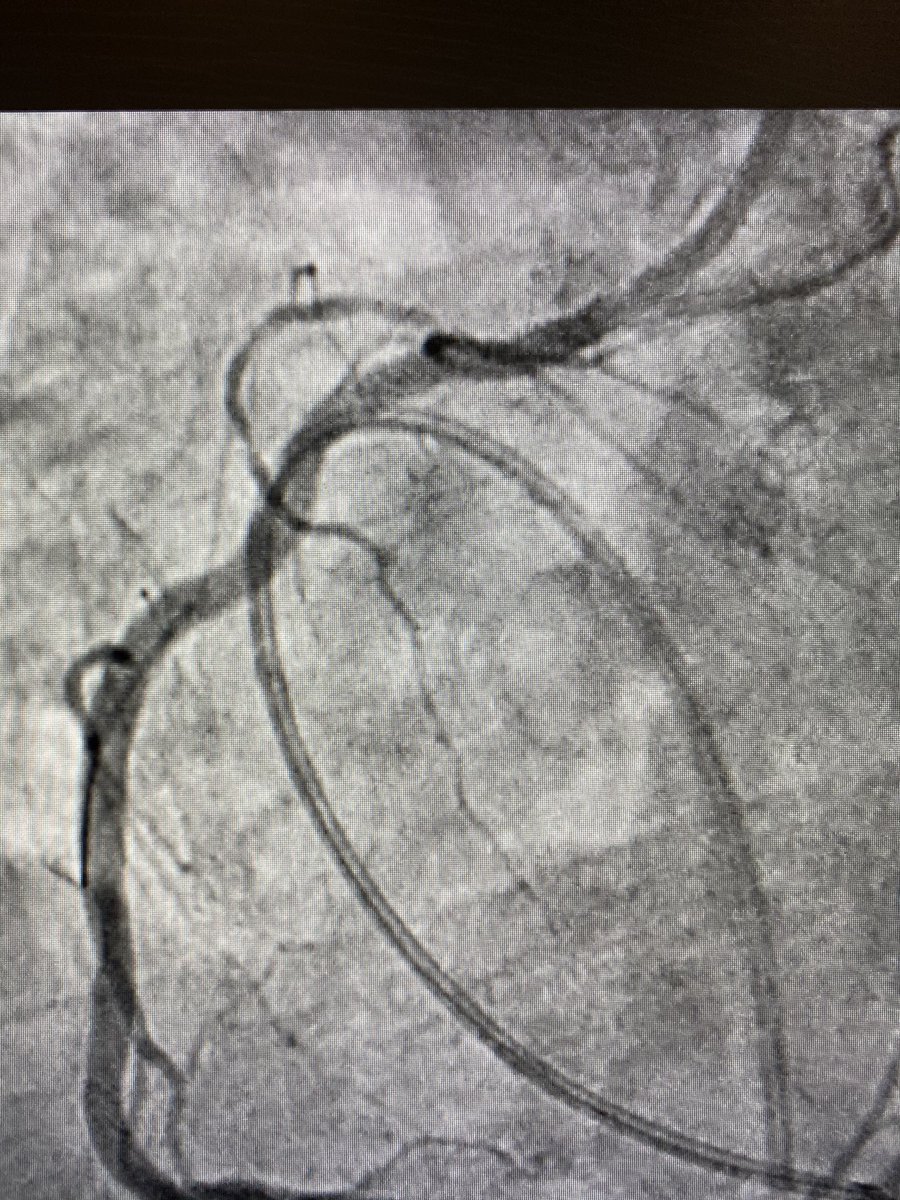

After considering making an early transition to industry but struggling to walk away from the lab, damn it feels good to get the #CHIP train rolling again! 1st #PercAx LM #rotapro in NJ & single #safefemoral access with 7fr dest via CP. Off-label but 💯! Props to @jason_wollmuth

RajTayalMD's tweet image. After considering making an early transition to industry but struggling to walk away from the lab, damn it feels good to get the #CHIP train rolling again! 1st #PercAx LM #rotapro in NJ & single #safefemoral access with 7fr dest via CP. Off-label but 💯! Props to @jason_wollmuth